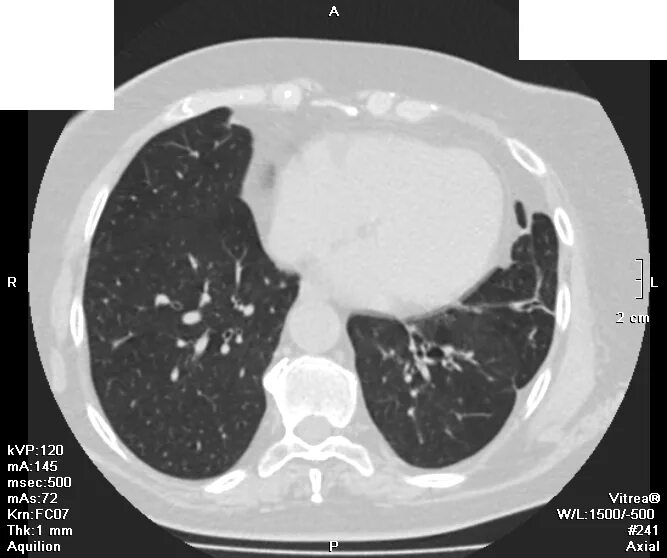

Грыжи на кт